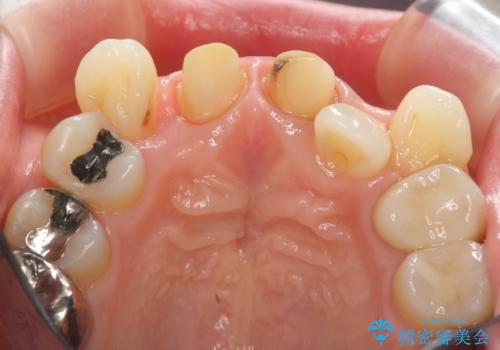

- 前歯の変色の改善を希望され来院されました。

X線写真より、充填剤の突き出た状態の根管治療の再治療を行い、セラミック治療を計画すると同時に、

歯ブラシがしづらく虫歯の原因となっている歯の位置の悪い右上側切歯の抜去を行います。